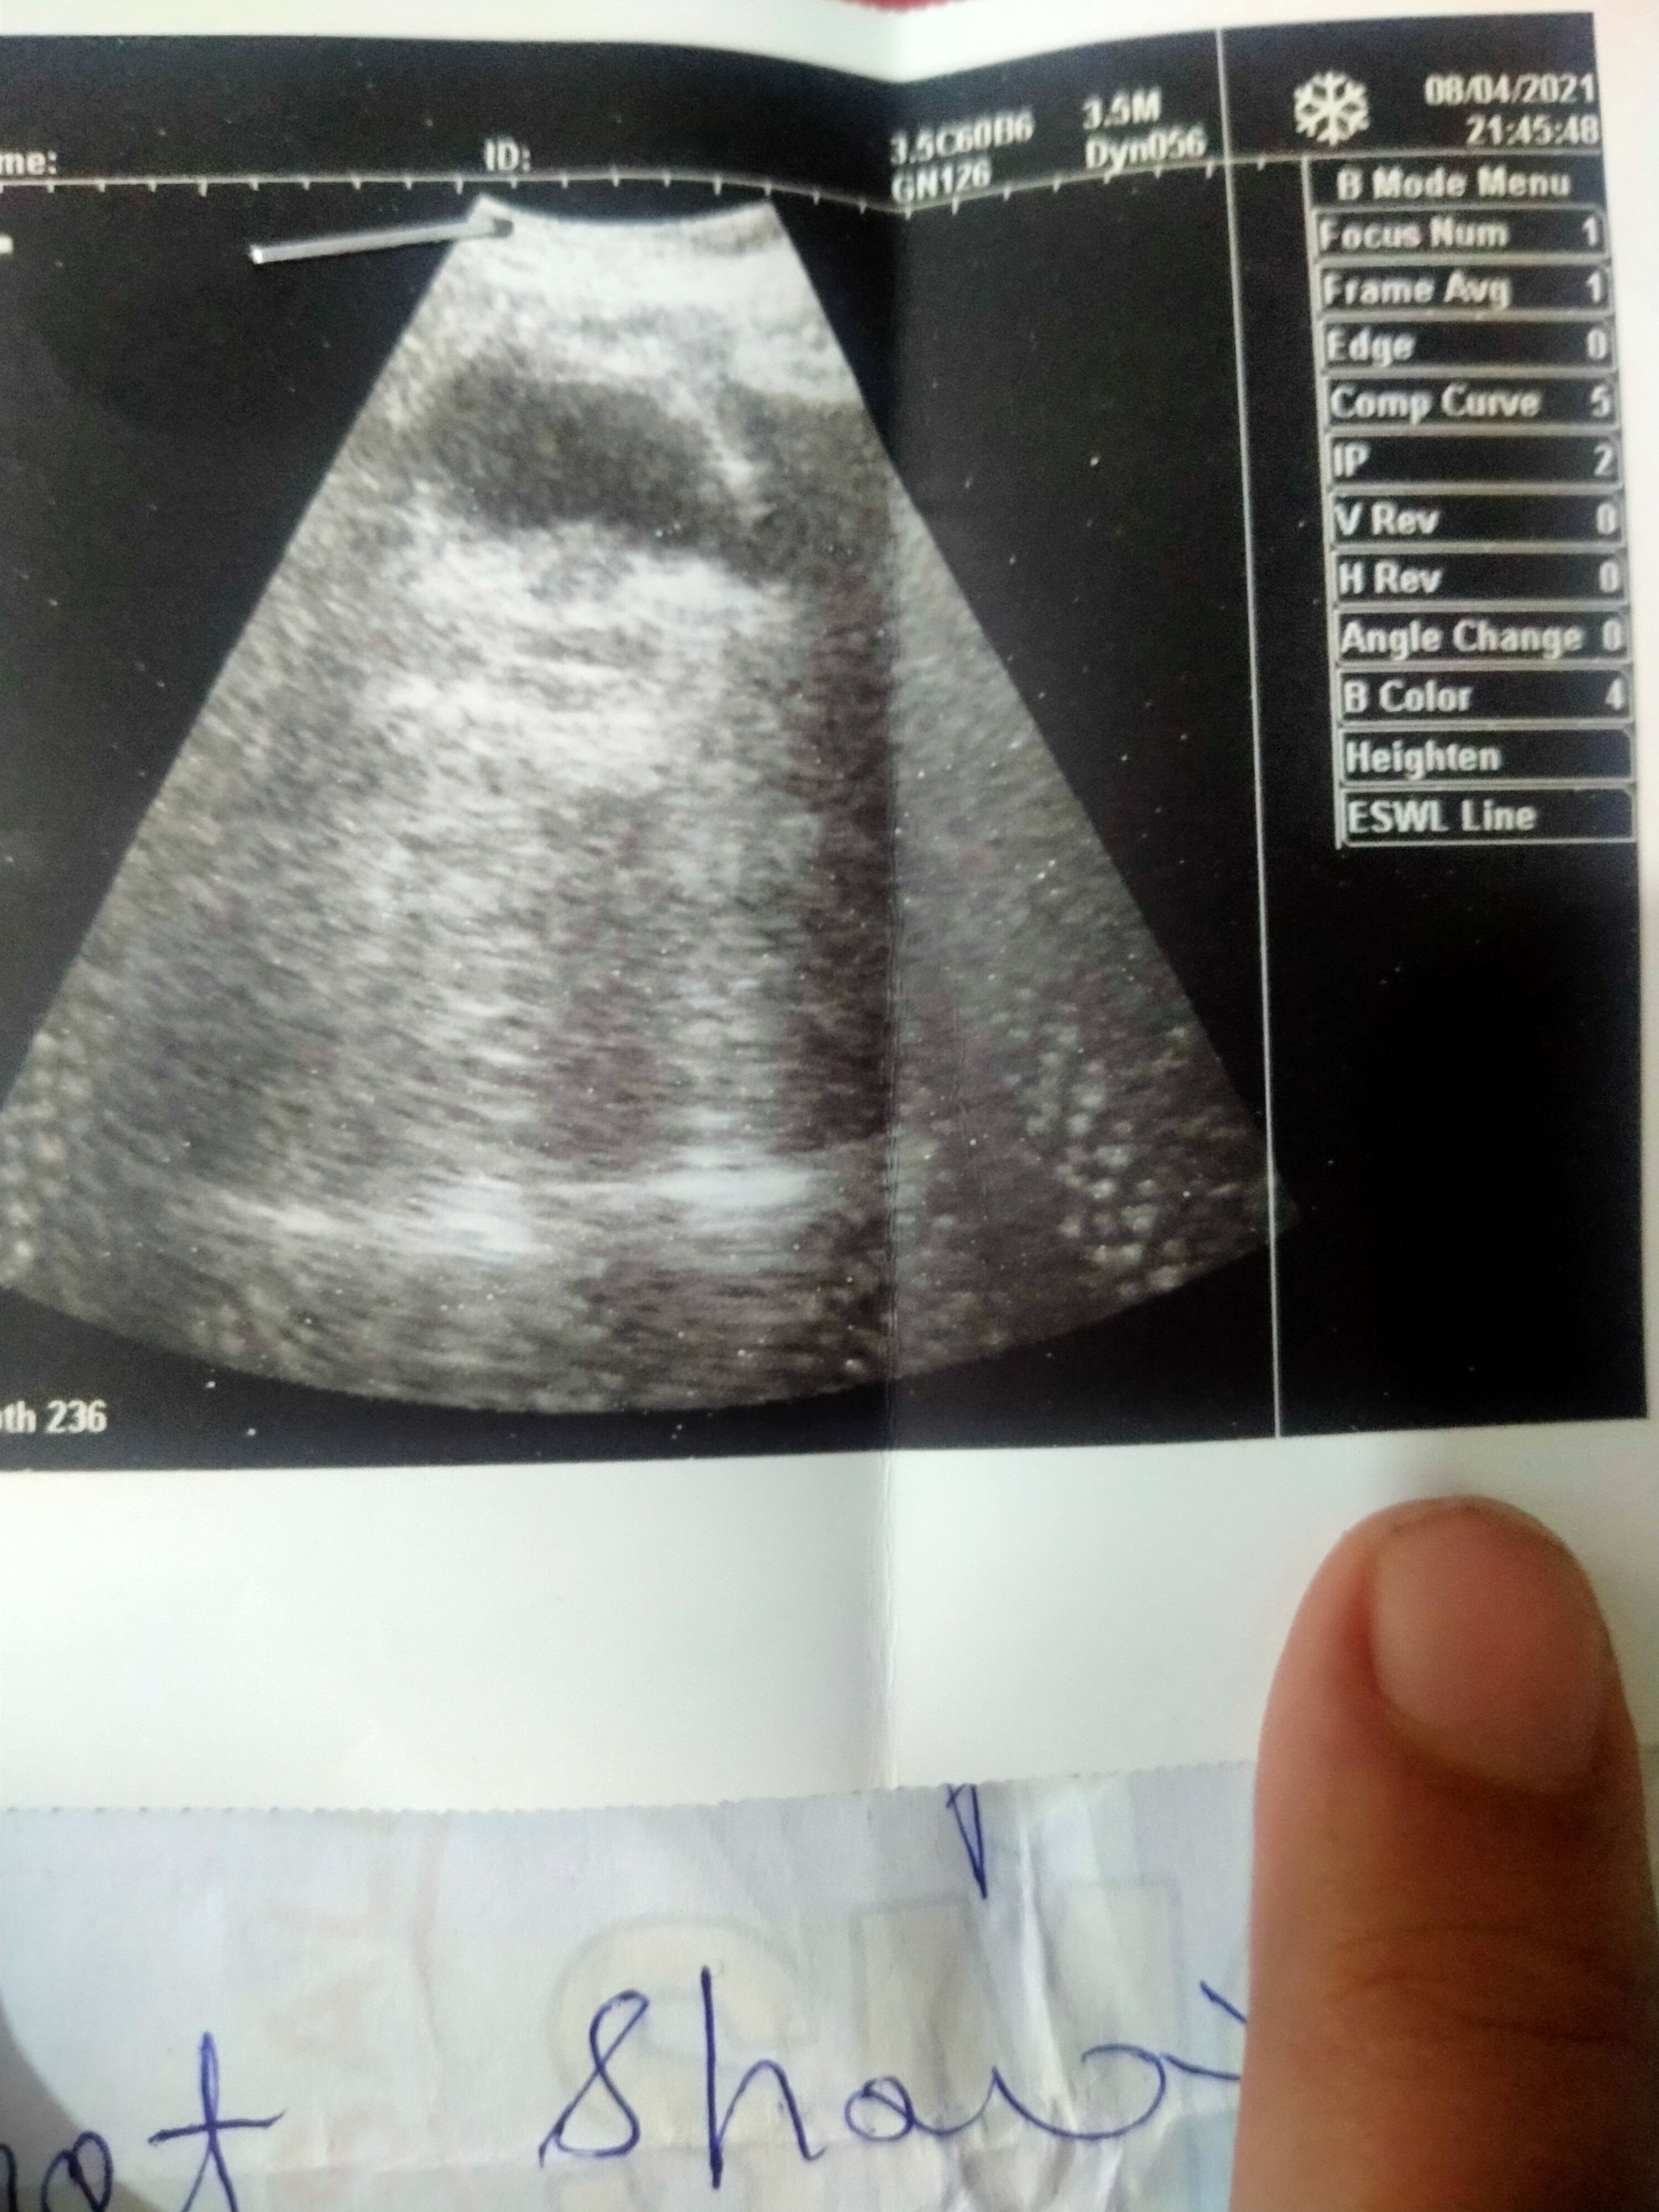

Irregular periods from 5 months, Last periodod date is 1st june, negative on strip test No pregnancy shown in ultrasound, doctor said endometrium is thickened I took primulute n for 3 to 4 days and stopped taking it on sunday morning, still i didn't get my period

Yes, it didn't show pregnancy and showed thick endometrium